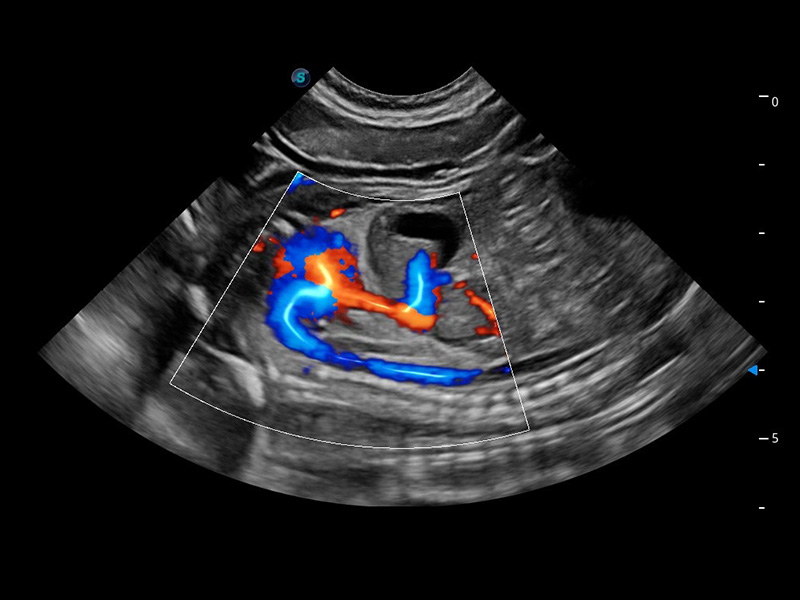

ProPet 60 作为一款高端台式动物超声设备,为动物医生的日常诊断提供了一系列贴合动物临床需求、解决临床实际问题的高级成像功能。凭借全系列高清探头,满足医生对腹部、心脏、生殖、浅表、肌骨等成像的所有需求,切实帮助您提升检查效率,提高诊断信心。

兽用彩色多普勒超声诊断系统